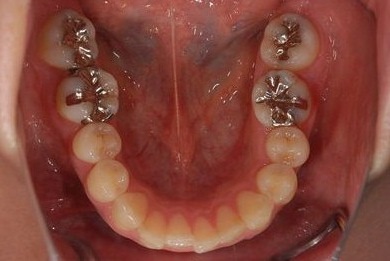

治療前

• 治療前